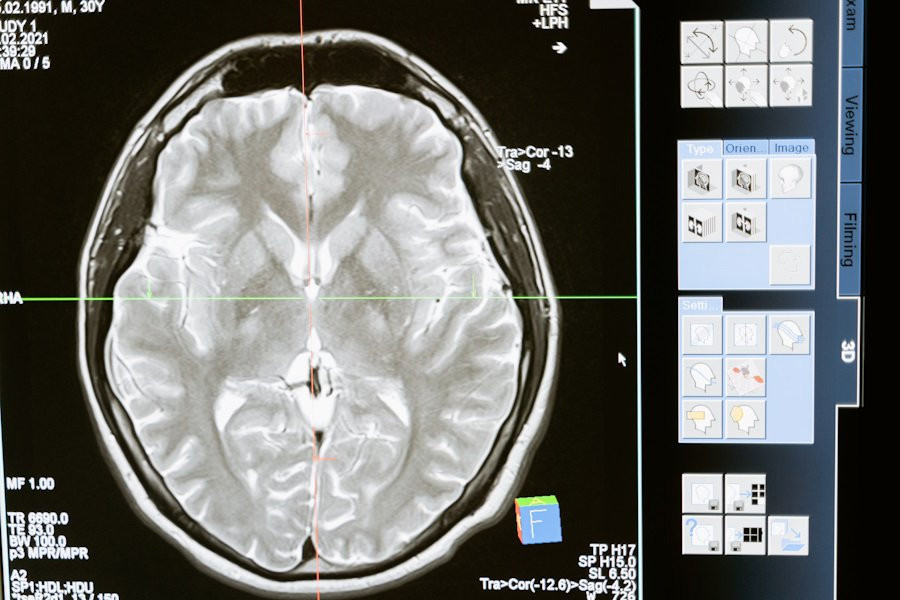

Фото из открытых источников

В исследовании психологов University of North Carolina была протестирована новая замкнутая система для измерения и стимулирования электрических паттернов мозга у пациентов с тяжелым депрессивным расстройством. Результаты показали значительное улучшение симптомов у большинства участников, сообщает Medical Xpress.

Наш мозг активно генерирует электрические сигналы в различных ситуациях, будь то физическая активность, еда или отдых. В состоянии покоя, когда мы думаем или просто расслабляемся, преобладают альфа-колебания на частоте 8–12 Гц. У пациентов с депрессией часто наблюдается нарушение равновесия этих альфа-волны в префронтальной коре, особенно в левой части.

Для решения этой проблемы учёные разработали замкнутую систему, способную измерять индивидуальные альфа-частоты и стимулировать мозг слабым переменным электрическим током. Этот метод направлен на восстановление нормального баланса альфа-колебаний.